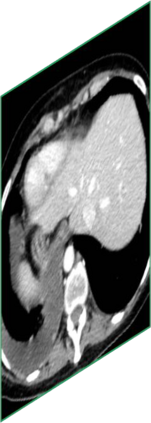

Due to the constraints of the imaging device and high cost in operation time, computer tomography (CT) scans are usually acquired with low intra-slice resolution. Improving the intra-slice resolution is beneficial to the disease diagnosis for both human experts and computer-aided systems. To this end, this paper builds a novel medical slice synthesis to increase the between-slice resolution. Considering that the ground-truth intermediate medical slices are always absent in clinical practice, we introduce the incremental cross-view mutual distillation strategy to accomplish this task in the self-supervised learning manner. Specifically, we model this problem from three different views: slice-wise interpolation from axial view and pixel-wise interpolation from coronal and sagittal views. Under this circumstance, the models learned from different views can distill valuable knowledge to guide the learning processes of each other. We can repeat this process to make the models synthesize intermediate slice data with increasing inter-slice resolution. To demonstrate the effectiveness of the proposed approach, we conduct comprehensive experiments on a large-scale CT dataset. Quantitative and qualitative comparison results show that our method outperforms state-of-the-art algorithms by clear margins.